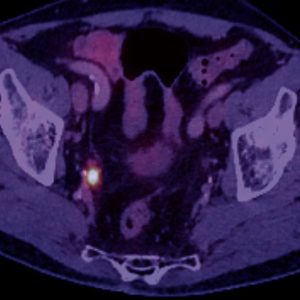

Willkommen zum 16. Petersberger Symposium – dem zentralen Treffpunkt für Expertinnen und Experten der klinischen Radiologie. Unter dem Motto „Radiologie meets Urologie“ widmen wir uns 2026 der Zukunft des Prostata-Screenings: von technischer Innovation über künstliche Intelligenz bis hin zu neuen diagnostischen und therapeutischen Standards.

Moderne Therapie und Rezidiv-Management

• Minimalinvasive Therapieansätze

• Rezidiv-Erkennung und Nachsorge